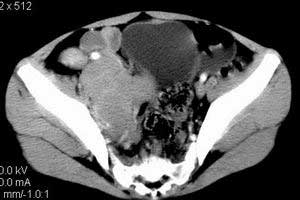

| 患者,男,9岁,因右下腹包块入院,血象不高,不规则发热,常超40度。 平扫: ![]() ![]() ![]() ![]() ![]() ![]() ![]() ![]() ![]() ![]() ![]() ![]() ![]() ![]() ![]() ![]() ![]() ![]() 增强: ![]() ![]() ![]() ![]() ![]() ![]() ![]() ![]() ![]() ![]() ![]() ![]() ![]() ![]() jiajie发言:骶椎右前区不规则软组织肿块,边缘光整,密度均匀,增强后均匀强化,右腹股沟区可见肿大淋巴结,临床有时发热,考虑淋巴瘤,儿童盆腔肿瘤应与神经母细胞瘤和横纹肌肉瘤鉴别。 longzhanghui发言:印象:盆腔右后壁不规则软组织肿块,并向前延伸.似为多个肿块融合,呈中等强化.初步考虑淋巴瘤. 听蝉观竹发言:右侧髂内、外组淋巴结肿大,从其形态和融合的情况看,同意大家意见-----考虑恶性病变,但是9岁男孩还要注意检查睾丸情况,有无隐睾? 常常类似情况是隐睾发生精原细胞瘤淋巴结转移,这个病例也要注意这一点!!! 广东凌发言:大家好,在这里我想说一下个人观点,我建议上传图片的同志能否辛苦一点就是把病史和图片都上传完整一点,比如这个病人的腹膜窗,并且这个病人的肠道的准备也是不怎么好,就从现有的质料看:病灶属于淋巴结肿大当无大的争议,有融合趋势,其内无坏死,边缘强化为主,故考虑:淋巴瘤!建议用腹膜窗看一下和肠道的关系! 阿圣发言:病灶属于淋巴结肿大当无大的争议,有融合趋势,其内无坏死,边缘强化为主,故考虑:淋巴瘤 结果是:淋巴瘤 病例来源:ct762。由宁静致远发布: http://www.radinet.com.cn/forum_view.asp?forum_id=4&view_id=2182 |